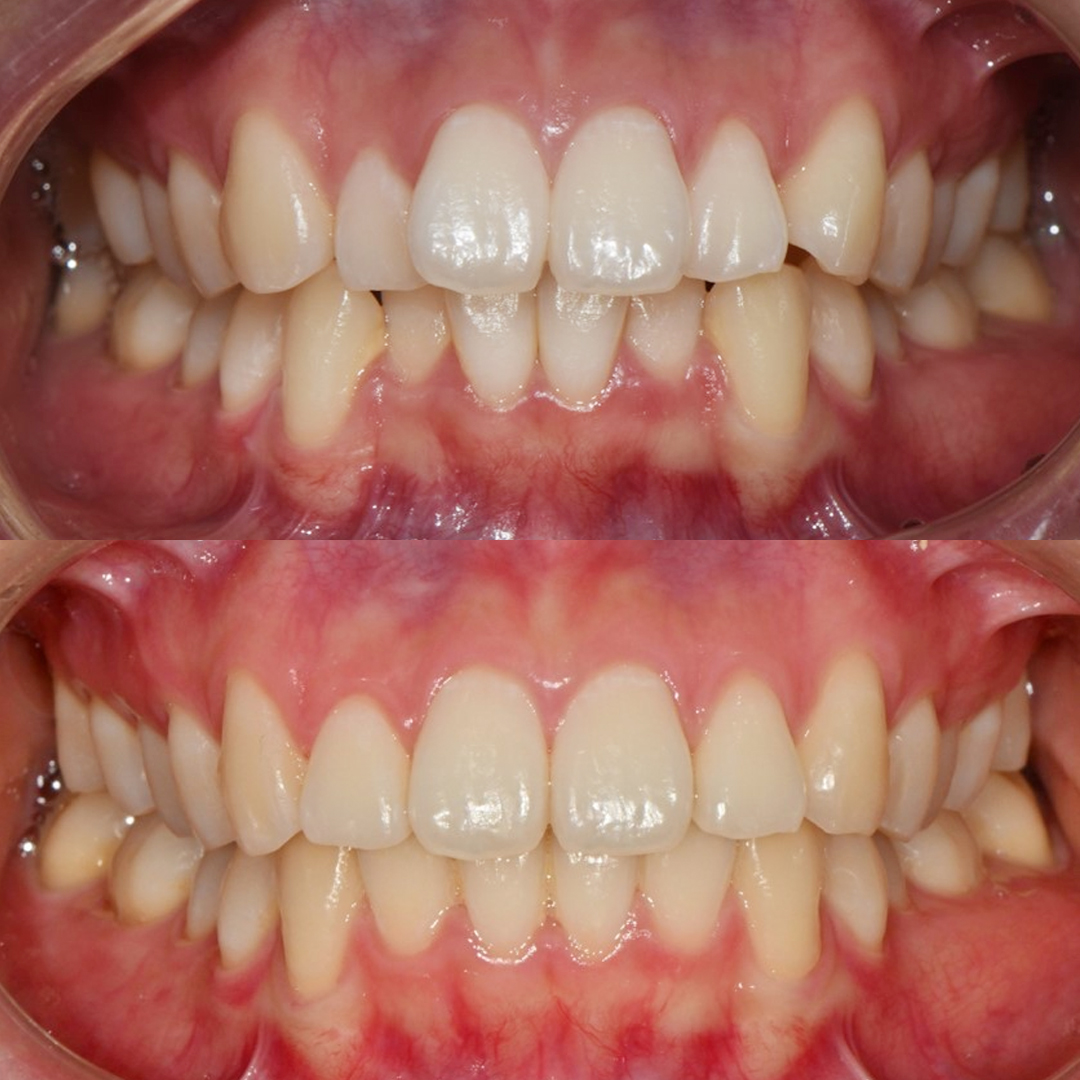

- 임플란트

- 심미보철

평균 악당 30분의 빠른 식립시간, 치료 케이스 다수 보유

전체 임플란트

상·하악 전체 치아를 대체하는 임플란트로 최소한의 식립을 통해

자연치아와 비슷한 기능을 수행할 수 있도록 합니다.